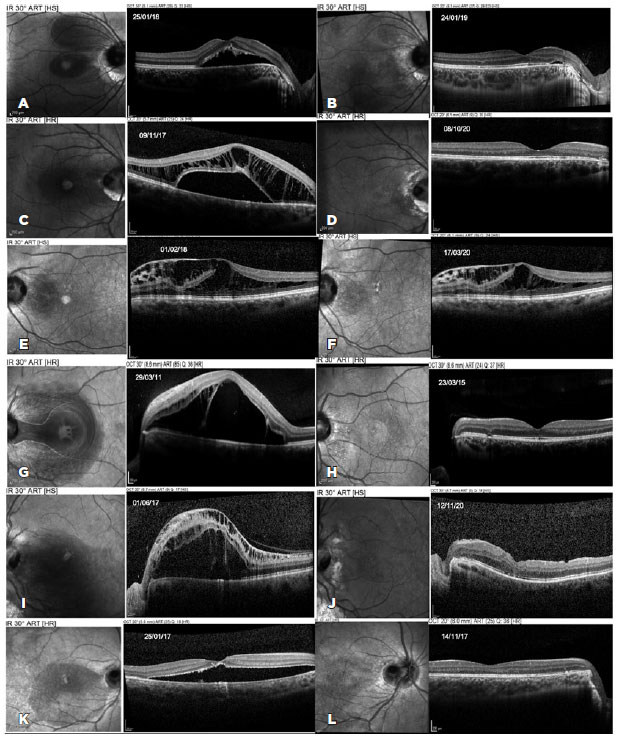

Postoperatively, OCT demonstrated complete fluid resolution in five patients, without recurrence during follow-up (Figure 1). Total reabsorption was documented after 12 months, 13 months, 25 months, and 6.5 months in patients number 1, 2, 4, and 6, respectively. Patient number 5 failed to demonstrate fluid reabsorption on OCT and underwent pars plana vitrectomy, achieving complete fluid resolution 41 months after the initial treatment. Patient number 3 failed to demonstrate progressive fluid reabsorption and refused any additional treatment.

08-fig01tb.jpg)

Clinical examination of patient number 4 showed a possible optic disc pit in the right eye (contralateral eye), which was confirmed on OCT (Figure 1). Cases of optic disc pit not associated with maculopathy should not be treated prophylactically with laser along the temporal optic disc margin. The natural history of this disease may not involve maculopathy development, and the risk of injury to the papillomacular bundle does not justify this approach(2).